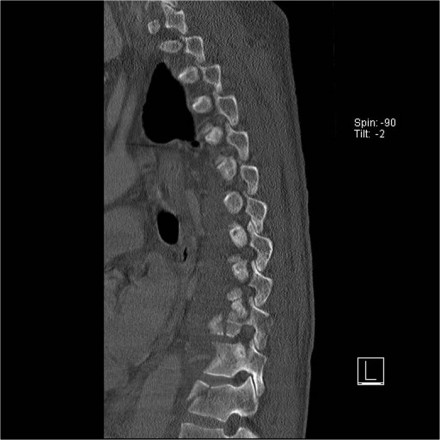

The images are of a patient with a typical bamboo spine as a result of ankylosing spondylitis.

After a fall on his back no fracture was seen on the x-rays.

However the CT shows a thin fracture line through the anterior side of the vertebral body and also through the spinous process.

Continue with the MR-images.